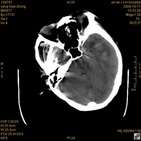

病人杨XX,男,青云街道办事处路踏泉村,住院号51666,CT号:104770。病人因“高血压脑出血”在新泰市人民医院住院治疗5天,治疗效果不佳转入我院,复查CT示左基底节血肿,病人昏迷状态,给予血肿清除术,术后2天复查CT,血肿完全清除,病人恢复好,治疗效果满意。附病人术前术后CT片资料如下。

术前CT

术前CT1 术前CT2 术前CT3 术前CT4